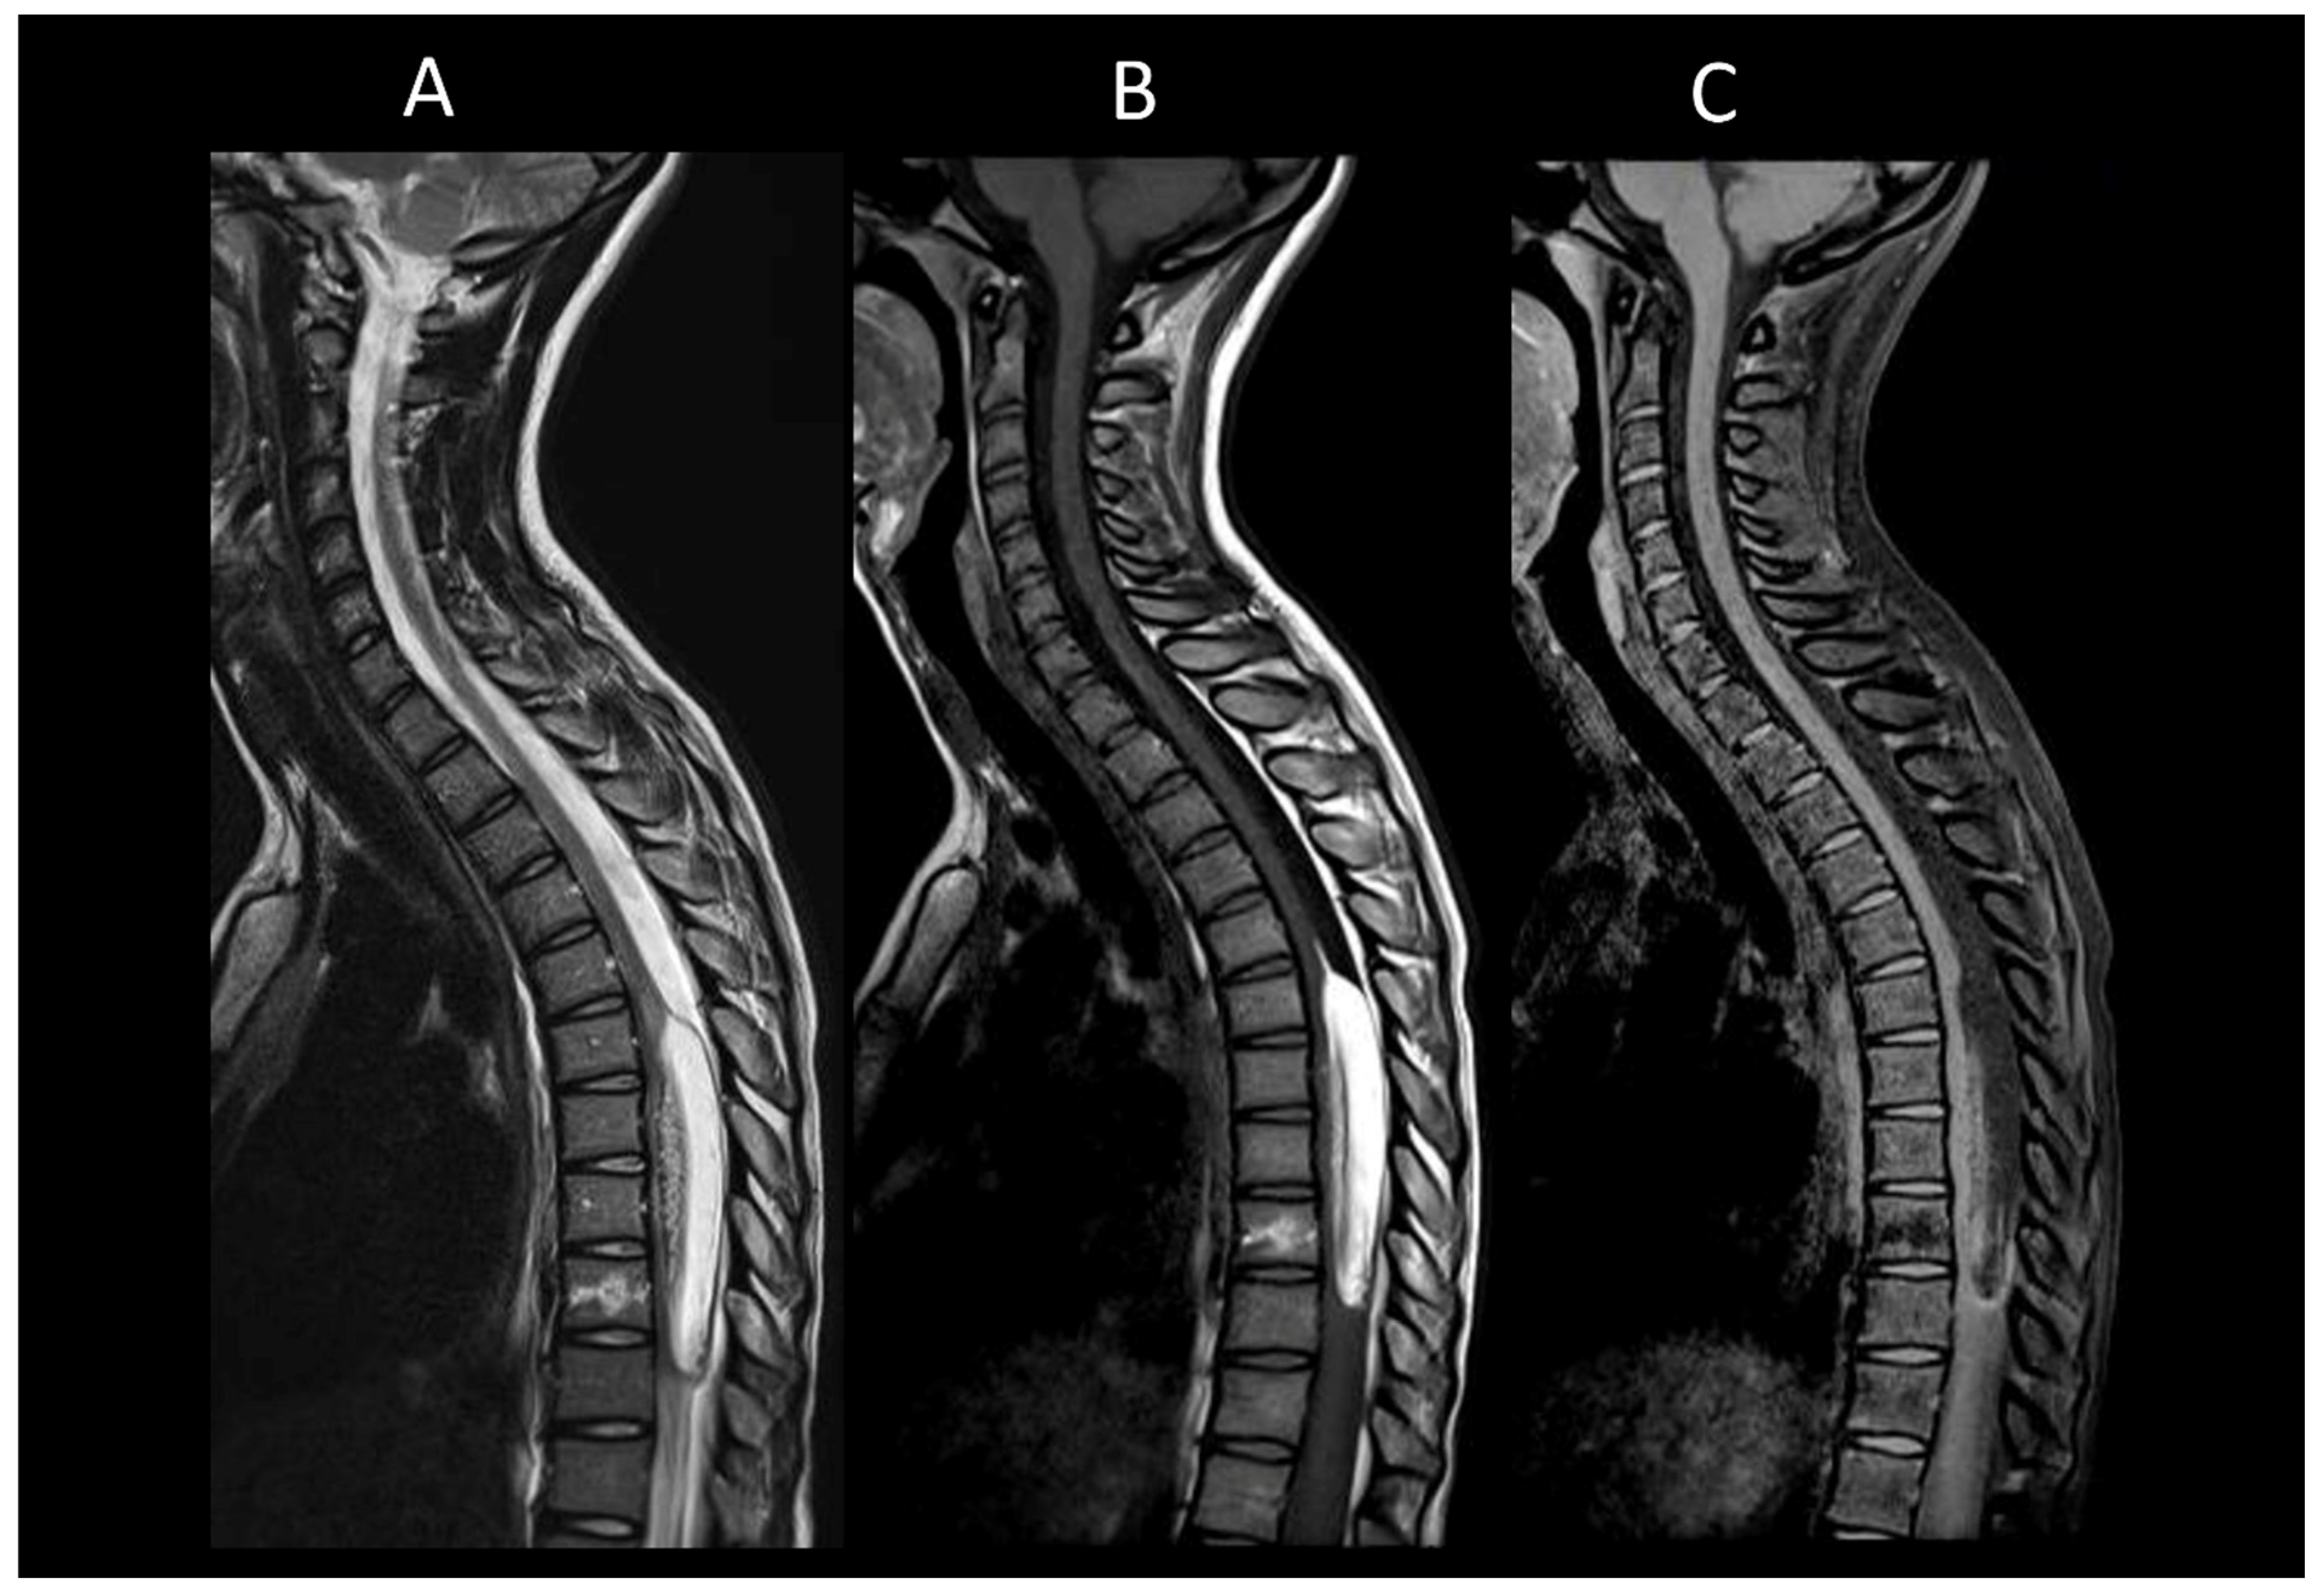

3.2. Degenerative Compressive Myelopathy

- Badhiwala, J.H.; Ahuja, C.S.; Akbar, M.A.; Witiw, C.D.; Nassiri, F.; Furlan, J.C.; Curt, A.; Wilson, J.R.; Fehlings, M.G. Degenerative Cervical Myelopathy—Update and Future Directions. Nat. Rev. Neurol. 2020, 16, 108–124. [Google Scholar] [CrossRef]

- Mehalic, T.F.; Pezzuti, R.T.; Applebaum, B.I. Magnetic Resonance Imaging and Cervical Spondylotic Myelopathy. Neurosurgery 1990, 26, 217–226. [Google Scholar] [CrossRef]

- Kim, H.J.; Tetreault, L.A.; Massicotte, E.M.; Arnold, P.M.; Skelly, A.C.; Brodt, E.D.; Riew, K.D. Differential Diagnosis for Cervical Spondylotic Myelopathy: Literature Review. Spine 2013, 38, S78–S88. [Google Scholar] [CrossRef]

- Nouri, A.; Martin, A.R.; Mikulis, D.; Fehlings, M.G. Magnetic Resonance Imaging Assessment of Degenerative Cervical Myelopathy: A Review of Structural Changes and Measurement Techniques. Neurosurg. Focus. 2016, 40, E5. [Google Scholar] [CrossRef]

- Ozawa, H.; Sato, T.; Hyodo, H.; Ishii, Y.; Morozumi, N.; Koizumi, Y.; Matsumoto, F.; Kasama, F.; Aizawa, T.; Itoi, E.; et al. Clinical Significance of Intramedullary Gd-DTPA Enhancement in Cervical Myelopathy. Spinal Cord. 2010, 48, 415–422. [Google Scholar] [CrossRef]

- Wang, Y.; Newsome, S.D. Cervical Spondylotic Myelopathy Mimicking Transverse Myelitis. Mult. Scler. Relat. Disord. 2019, 31, 131–133. [Google Scholar] [CrossRef] [PubMed]

- Flanagan, E.P.; Krecke, K.N.; Marsh, R.W.; Giannini, C.; Keegan, B.M.; Weinshenker, B.G. Specific Pattern of Gadolinium Enhancement in Spondylotic Myelopathy. Ann. Neurol. 2014, 76, 54–65. [Google Scholar] [CrossRef]

- Syc-Mazurek, S.B.; Montenegro, M.; Clarke, M.J.; Flanagan, E.P. MRI with Neck Extension to Diagnose Cervical Spondylotic Myelopathy. Pract. Neurol. 2022, 22, 162–163. [Google Scholar] [CrossRef] [PubMed]